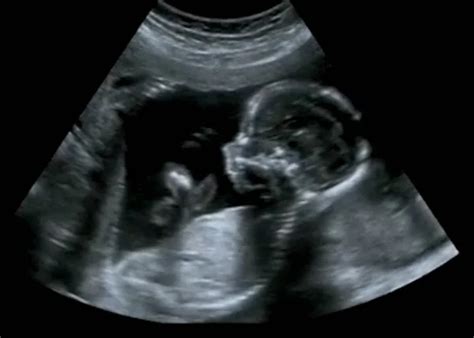

A baba neme általában a 14-16. hét környékén már ultrahanggal is megállapítható. Azonban ez nem mindig 100%-os pontosságú. A nemi dudor 9 hetesen kezd formálódni, pénisszé vagy csiklóvá. Körülbelül 12 hetesen már valószínűsíthető a baba neme ultrahang alapján a nemi dudor szögéhez igazodva - ez az ún. „nub elmélet”.

Magzati nem meghatározása ultrahanggal | Baba nemének meghatározása ultrahanggal (fiú/lány)

A baba neme már a megtermékenyülés pillanatában eldől. Az ultrahangvizsgálat elsősorban a terhesség és a baba fejlődésének követésére szolgál, nem neme meghatározására, de nagy pontossággal mégis alkalmas annak kiderítésére is. Bár elvileg akár már 12 hetesen is megállapítható a nem, több tényező is befolyásolja, hogy ez tényleg sikerül-e: a babának jó pozícióban kell lennie az ultrahanghoz; előfordulhat, hogy nincs idő megvárni, míg a baba megfelelő helyzetbe fordul.